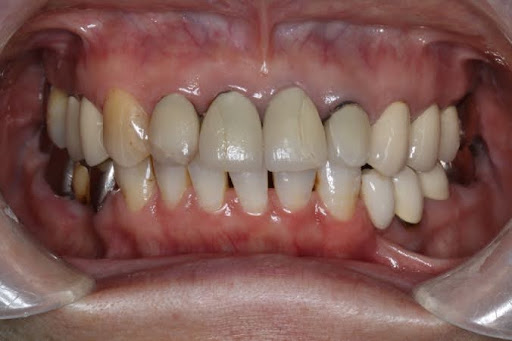

症例